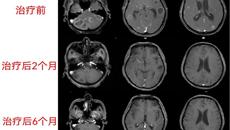

2021年初,家住南宁的陈老伯突然出现剧烈头痛,并伴有脑部昏沉感、行走不稳,起初陈老伯不以为意,认为是自己没休息好或受凉引起,可出乎他意料的是,头痛的症状竟一天比一天严重。1月9日,陈老伯终于无法忍受剧烈的痛楚,家人赶紧将他送至家附近的医院,经头颅CT检查,提示脑内多发囊实性病变,性质暂时不明,于是给他开了几天的对症口服药物,可陈老伯服药后头痛症状非但没有缓解,还出现了恶心、呕吐等症状。医院在给陈老伯...01.042022